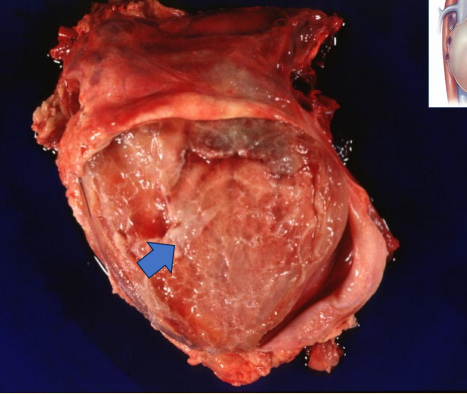

What does this image show?

bovine heart with traumatic pericarditis

What happens in a bovine heart with traumatic pericarditis?

cells organised and converted into fibrous tissue

fibrous tissue is firmly attached and forms adhesions between surfaces